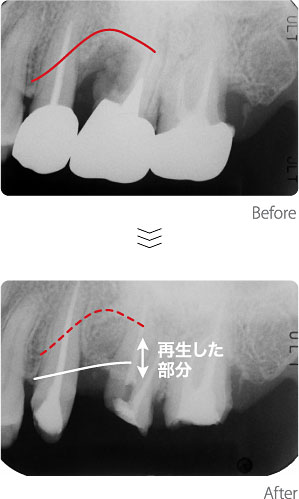

歯周病治療〈Case2〉

歯ぐきの内部の根の表面で細菌が繁殖し、周囲の骨が失われつつありました。原因である細菌を除去し、骨を再生する処置を施しました。骨が無くなってしまい黒く写っている部分に、新しい骨が再生している事がわかります。